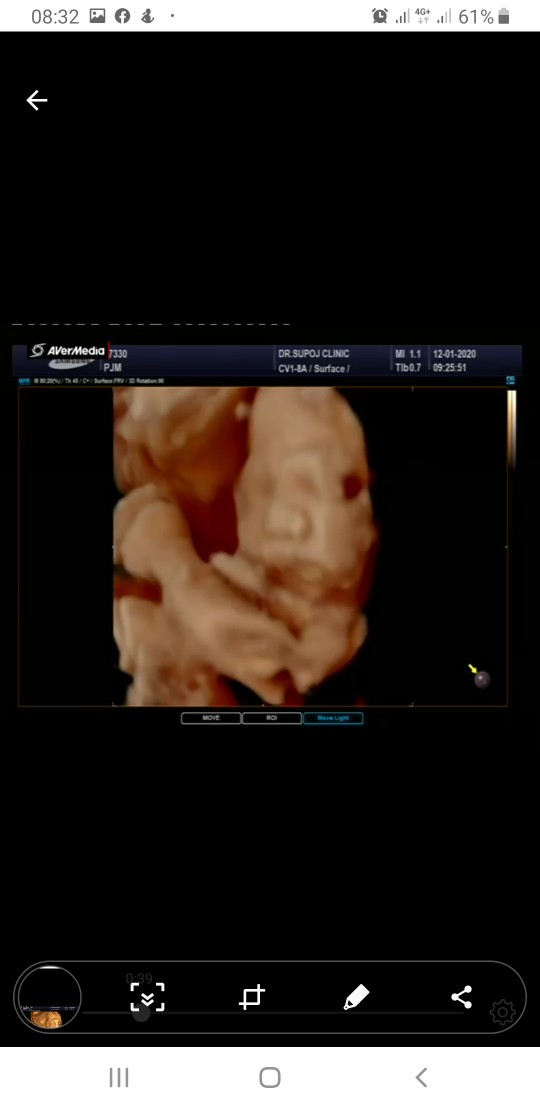

ครั่งแรกที่เหนค่ะ